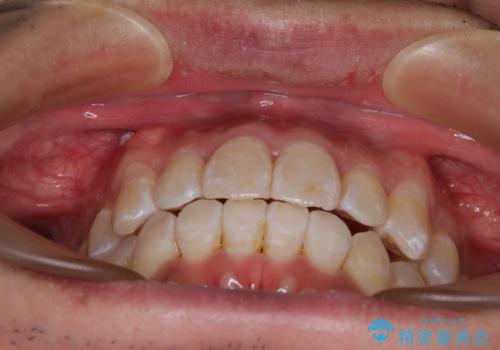

- 前歯のデコボコとクロスバイトを気にして来院された患者様です。

40代半ばであり、あまり周りに気を遣われずに治療を進めたいとのことで、インビザラインにて矯正治療を行うこととしました。

毎日22時間の装着時間をきっちりと守ってくださり、1年半かけずに思い通りの歯列に仕上げることができました。